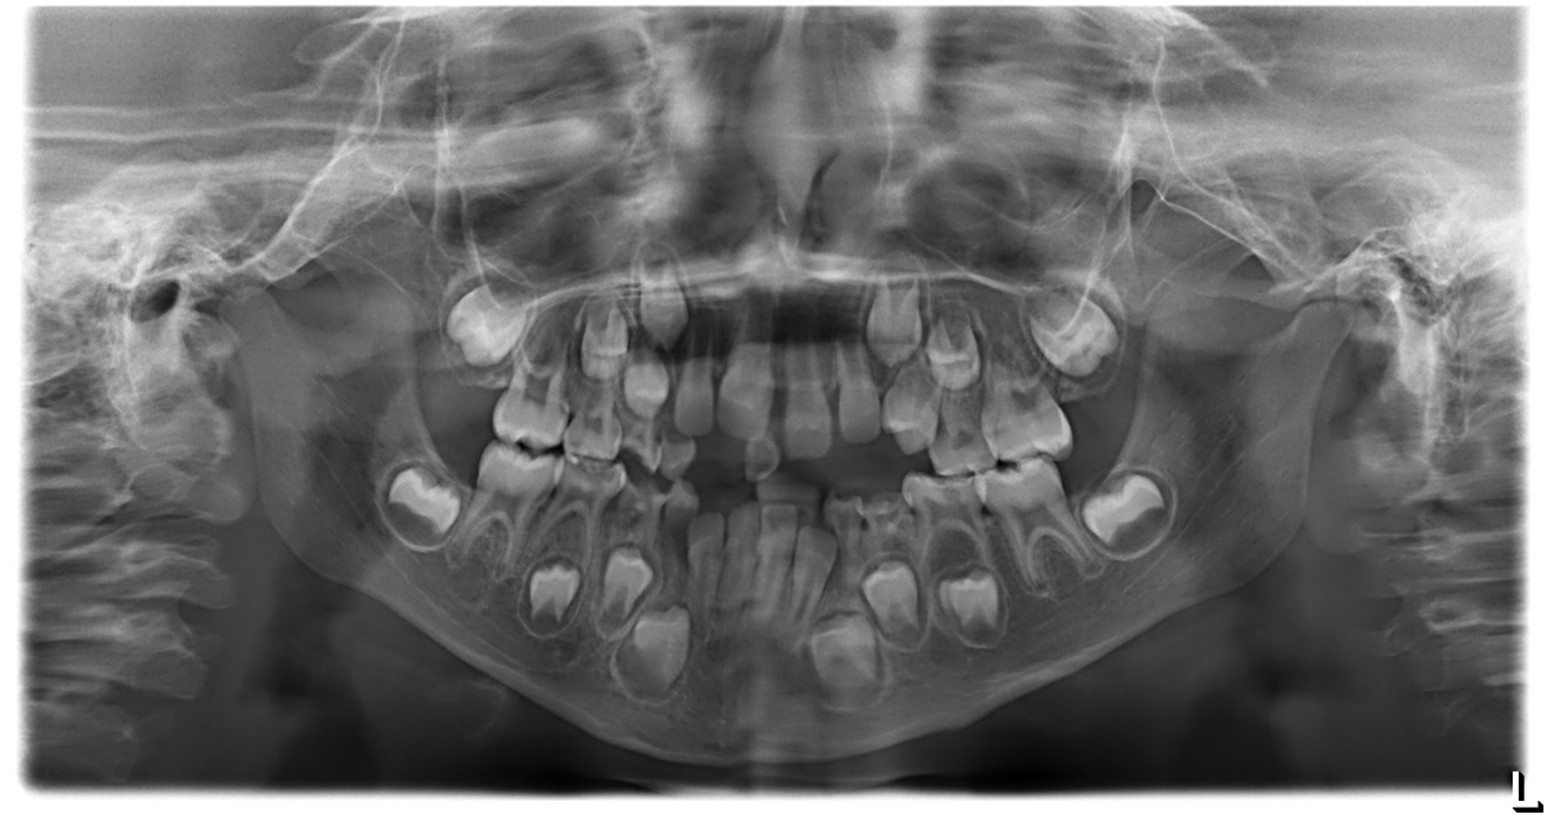

Figure 2: Panoramic radiograph (OPG). According to the AAPD Guidelines for Prescribing Dental Radiographs, for a new patient in the mixed dentition stage being evaluated for dental disease and development, an individualized radiographic examination should include a panoramic radiograph with posterior bitewings and/or selected periapical views. The present panoramic image shows a straight nasal septum with normal nasal passages, intact maxillary sinuses, and symmetrical right and left condyles. The inferior border of the mandible appears intact, and the bone trabecular pattern is normal. The patient’s dental age corresponds approximately to the chronological age, with a complete complement of teeth and no supernumerary teeth. No pathological or structural abnormalities were detected.